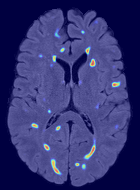

Patch size is another important parameter of the network. In computer vision applications such as object detection, usually a whole 2D image is used as a feature. However, full 3D medical images can not typically be used because of memory limitations. Fig. 4 shows examples of lesion memberships obtained with different sized 2D patches. As the patch sizes increases, the false positives that are mostly observed in the cortex tend to decrease. Fig. 5 shows a plot of Dice and LFPR with various patch sizes, ordered from left to right according to their increasing size. Note that smaller patches ( to ) produced significantly lower Dice and higher LFPR compared to other patches (), as seen from the memberships in Fig. 4. Also some of the highest Dice and lowest LFPR were observed for patches with large in-plane size, i.e., , , and . It was observed in Fig. 5 that there is no significant difference between Dice coefficients for , , or , but LFPR of both and are significantly lower than that of (). We chose as the optimal patch size. Other choices of smaller and patches (not shown) yielded worse results. Note that although training was performed with different patch sizes, the memberships were generated slice by slice, as the trained model consisted only of convolutions and did not need any information about patch sizes.

In our experiments, we used large 2D patches similar to Ghafoorian et al. (2017b), in comparison to isotropic 3D patches as used before, e.g., in Valverde et al. (2017), in Wachinger et al. (2017), and in Kamnitsas et al. (2017). The rationale behind using large anisotropic patches is twofold. First, experiments with full 3D isotropic or patches showed little or no improvement in Dice and led to increased false positives, with memberships similar to the one with patches, as shown in Fig. 4. Larger isotropic patches, e.g. or , showed inferior segmentation, and in some cases, optimization did not converge. The reason is that the FLAIR images in the test datasets had inherently low resolution in the inferior-superior direction, mm and mm compared to in-plane resolution of mm. Therefore 2D axial patches capture the high resolution in-plane information that represents the original thick axial slices. Second, the lesions are usually focal and small in size, unlike other brain structures. Therefore a very large isotropic patch around a small lesion can include superfluous information about the lesion, which can increase the amount of false positives. Note that with in more recent studies employing high resolution 3D FLAIR sequences, it is trivial to extend the algorithm to accommodate for 3D patches.